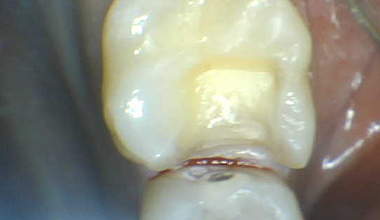

CASE 01

치료 전 -

치료 중 -

치료 후